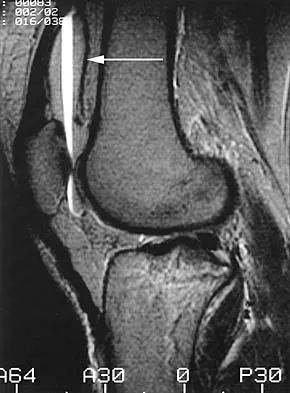

A 45-year-old male karate instructor sustained the injury shown in Figures 40a through 40c while practicing karate. The decision to proceed with surgery depends on which of the following factors?

The most important criteria in determining the need for surgery following a nondisplaced or minimally displaced tibial plateau fracture is knee stability to varus/valgus stress. Soft-tissue injury noted on MRI may be addressed at a later time following fracture healing. This fracture pattern is amenable to nonsurgical management. Decisions regarding surgical intervention may be made up to 2 weeks after injury.